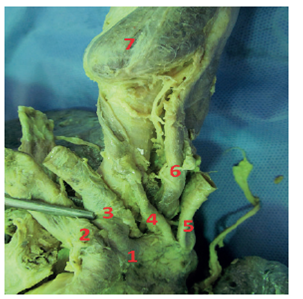

The dissection process was performed by removing fatty tissue and the pericardium covering the ascending aorta, the aortic arch and the blood vessels in the aorta. Then, the vascular diameters of the aortic arch were measured with a digital caliper (Figure 1). Throughout the process, photographic evidence was taken using a Nikon 1 J5 camera.

The most frequent type of AA in the sample was Type I or usual pattern (Figure 2) with 74.29% (n = 26). The Type II AA or bovine arch (Figure 3) was found in 11.43% (n = 4) of the study population, Type III AA (Figure 4) in 8.57% (n = 3), Type V AA (Figure 5) in 3% (n = 1), and Type VIII AA (Figure 6) in 3% (n = 1). Types IV, VI and VII were not found in this study (Table 2).